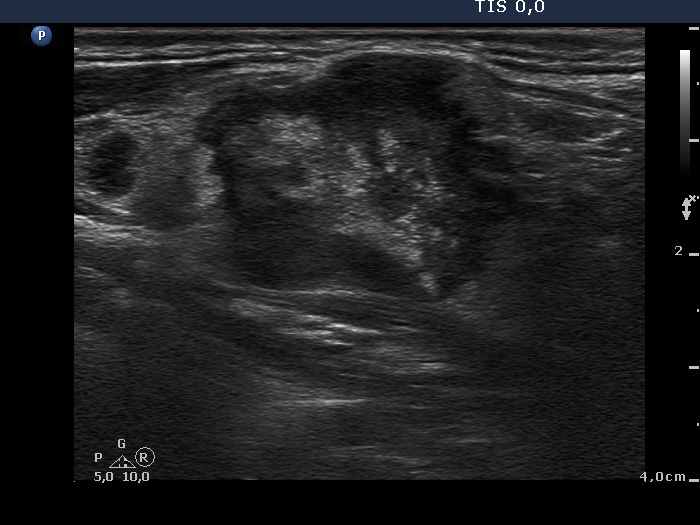

Ultrasonography: The thyroid was intact. There were multiple nodes in both supraclavicular regions. The nodes presented an absolutely irregular shape and border. They contained numerous hyperechogenic circumscribed areas.